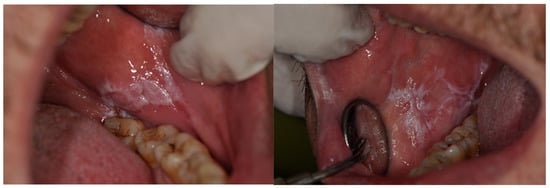

- According to the types and lesions pattern, oral mucosa pathologies are observed in different sites of oral cavity, both in single or multiple localizations and both symmetrically and non-symmetrically.